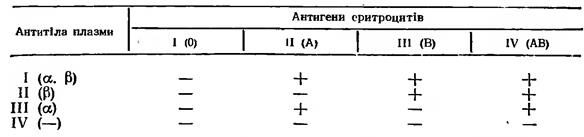

Визначення групи крові:

Методика визначення групи крові за стандартними сироватками:

Хід роботи:

- На чисту фарфорову тарілку нанести по краплі стандартних сироваток І, ІІ, ІІІ груп.

- В кожну краплю сироватки наносять краплю крові. \ Кров беруть щоразу чистим куточком предметного скельця у співвідношенні 10:1 \

- Визначення групи крові проводять на протязі 5 хв, періодично легенько поколихуючи тарілку.

- По мірі аглютинації \ не раніше ніж через 3 хвилини \ додати одну краплю ізотонічного розчину хлориду натрію.

- Продовжити спостереження до 5 хв.

- Через 5 хв зробити візуальне визначення наявності чи відсутності аглютинації.

ФІЗІОЛОГІЯ КРОВІ

Методика визначення групи крові за допомогою цоліклонів:

Цоліклони анти-А та анти-В використовують для визначення групи крові замість стандартних гемаглютинуючих сироваток. Виготовляються цоліклони з мишиних антитілоутворюючих В-лімфоцитів з клітинами мишиної мієломи. Це є розведена асцитична рідина мишей, що містить імуноглобулін М проти антигенів А та В. Цоліклони дають більш швидку та чітку реакію глютинації, ніж стандартні сироватки. При використанні цоліклонів виключається можливість передачі віруса гепатиту та ВІЧ (СНІДу).

Цоліклони анти-А і анти-В наносять на попередньо марковану спеціальним олівцем скляну пластину, по одній великій краплині (0,1 мл.) під відповідними надписами. Поряд з ними наносять в десять разів менші (0,01 мл) краплинки досліджуваної крові. Їх змішують скляними Можливі 4 варіанти реакції;

1) аглютинація з целіклонами анти-А і анти-В відсутня, антигенів А та В нема; досліджувана кров належить до І (0) групи;

2) аглютинація настала в пробі з целіклоном анти-А, в крові є антиген А; досліджувана кров належить до II (А) групи;

3) аглютинація спостерігається в пробі з целіклоном анти-В, в крові є антиген В; досліджувана кров належить до III (В) групи;

4) аглютинація настала в пробах з обома целіклонами - анти-А і анти-В, в крові містяться обидва антигени - А і В; досліджувана кров належить до IV (АВ) групи.

паличками.

Результати реакції оцінюють за наявністю або відсутністю аглютинації через 2,5 хв від початку змішування